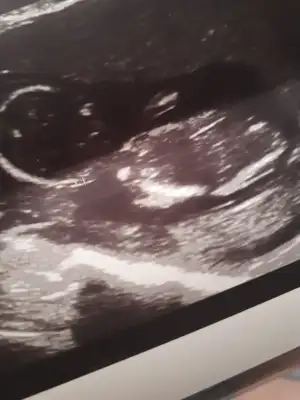

dr soylemeden siz gorun genital nub teorisi ( bebegin cinsiyeti)

Yaa Buda benim 10 haftalık miniğim , tahminde bulunabılır misiniz

Birisi vajinal birisi normal ultrason yorumlar misiniz 🙄